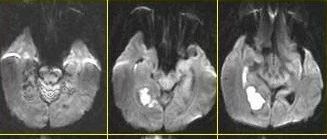

医学影像  yxyx-app  医学影像APP,打造伴随医生快速成长的影像学习社区。与影像园(Xctmr.com)一起提供最全面的影像案例库、基础(解剖、病理、影像诊断)知识、影像技术及考题等,为医生提供最佳的医学影像参考。【所属科室】神经外科【基本资料】患者,男,59岁【主诉】头痛半月伴四肢乏力【现病史】患者半月前无明显诱因下出现头痛不适,以右枕部最明显,进行性加重,并出现恶心呕吐,为胃内容物,非喷射性,感四肢乏力,近四天无力行走。...

中枢神经系统感染的MRI表现,一文了解!

作者:Tsai在当前病毒侵袭及个体免疫缺陷的环境下,中枢神经系统(CNS)感染性疾病仍为全球高发病率和死亡率疾病,随着新型抗生素的发明及使用,大部分疾病得到了治愈。目前确诊需依靠病理学标准,不利于患者早期诊治,临床上常根据患者临床表现及辅助检查依据予经验性治疗,其中MRI检查显得尤为重要。本文根据病灶在T1、T2和增强序列上的特征对其进行分类,并分别阐述。图1 中枢神经系统感染的MRI表现环形增强病灶...

颅内环形强化,这种特征性表现你熟悉吗 ?

脑脓肿(brain abscess)是目前临床上较为严重的颅内化脓性感染疾病,感染途径有相邻感染病灶的传染、血行传播、隐源性感染及手术或颅脑外伤导致,其中隐源性 、血源性感染脑脓肿目前在整体脑脓肿的所占比例较高。脑脓肿以幕上多见,好发于皮质交界区,颞叶居多,其次是额、顶、枕叶,小脑半球和垂体囊肿少见,临床表现为全身感染症状和颅内压升高症状。病理脑脓肿的形成分为四个阶段:(1)脑炎早期:3~5 天,局灶性炎症,...